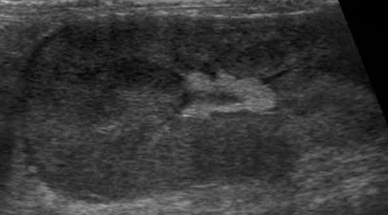

고양이의 신장은 매우 공 같으며, 개보다 유동성이 심합니다. 따라서 프로브를 통해 압박을 가할 때 신장이 빠져나가지 않게 조심스럽게 접근해야 합니다. 중간 주파수의 convex 프로브(7.5-9MHz)로 적절한 영상을 획득할 수 있으며, 더욱 자세한 영상을 얻기 위해서는 보다 높은 주파수의 linear 프로브(10-14MHz)를 이용할 수 있습니다. 그리고 신장은 서로 직각 방향의 방향에서 관찰하는 것이 중요합니다(그림 1 & 2).

정상 신장의 모양은 난원형 혹은 콩 모양을 보이며, 피질(cortex), 수질(medulla) 및 신동(sinus)으로 구분됩니다. 신장의 trans view에선 신우도 관찰할 수 있습니다. 피질은 균일한 에코를 가지며, 간과 비교 시 약간의 저에코 혹은 같은 동에코, 비장과 비교 시에는 저에코성을 보입니다. 정상 고양이에서 근위세뇨관 상피의 지방축적이 많으면 피질의 에코가 증가하여 간보다 에코성이 높아 보일 수 있고, 특히 노령묘, 거세한 수컷과 임신한 고양이에서 이런 현상을 보입니다. 수질은 저에코성~무에코성을 나타내며, 신동은 신문의 중심부로서 지방의 존재로 고에코성을 보입니다.

신우는 보통 보이지 않으나, trans view를 잘 잡으면 보일 수 있습니다(그림 2). 신우의 폭은 1-2mm로 무에코의 선으로 관찰됩니다. 수액 투여 시에는 일시적 확장이 있으며, 결석으로 인한 요도폐색, 종양, 이소성 요관이나 신우신염이 있을 때는 확장이 될 수 있습니다(Table 2, 그림 3). 또한 leptospirosis, 신장의 말기 상태나 신장이식 등에서도 나타날 수 있습니다3).